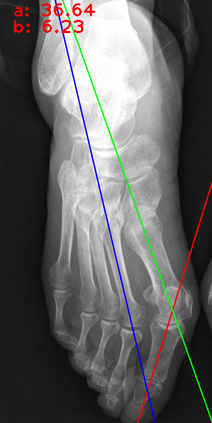

Angular measurements is essential to make a resonable treatment for Hallux valgus (HV), a common forefoot deformity. However, it still depends on manual labeling and measurement, which is time-consuming and sometimes unreliable. Automating this process is a thing of concern. However, it lack of dataset and the keypoints based method which made a great success in pose estimation is not suitable for this field.To solve the problems, we made a dataset and developed an algorithm based on deep learning and linear regression. It shows great fitting ability to the ground truth.